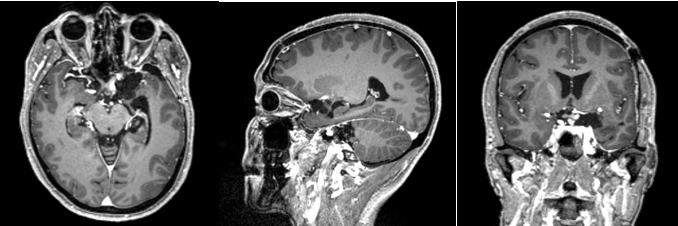

现病史:患者20天前无明显原因出现鼻酸,伴有异味感,继之出现全身不适,呈发作性,每次持续约1分钟左右,发作时意识清、精神可,对发病时情况记忆模糊,共发作3-4次,无意识模糊、复视。颅脑MRI平扫+强化示:鞍上池左侧可见不规则等T1等T2信号影,DWI呈等信号;明显均匀强化,与前床突、颈内动脉关系密切。

诊断:左侧蝶骨嵴脑膜瘤;继发性癫痫。

Al-Mefty教授根据肿瘤的起源和肿瘤与颈内动脉之间是否存在蛛网膜界面,将前床突-蝶骨嵴内侧的脑膜瘤分为三型,这是目前最为经典和广泛认可的分型。ICA在前床突内、下侧方从海绵窦穿出,经过内环与外环(或上环与下环)而后进入硬膜下腔,内外环之间约1-2mm,该节段缺少蛛网膜覆盖。起源于这一小段的脑膜瘤被分为1型前床突脑膜瘤。1型典型的生长方式是包裹ICA,并向颈内动脉分叉部方向生长,包裹近端大脑中动脉。由于肿瘤与颈内动脉之间缺乏蛛网膜,所以它紧密黏附在ICA的外膜上,以至于分离困难,导致手术治愈率相对较低。该患者主体属于1型前床突脑膜瘤,但是因其部分侵入视神经管内,兼有3型的特点,严格讲其属于1-3复合型脑膜瘤。该患者经左侧翼点入路肿瘤切除术,实现肿瘤近全切除,术后未再出现癫痫发作,脑电图无异常,后逐渐减用停用抗癫痫药物,现已持续随访4年余,未见肿瘤复发。